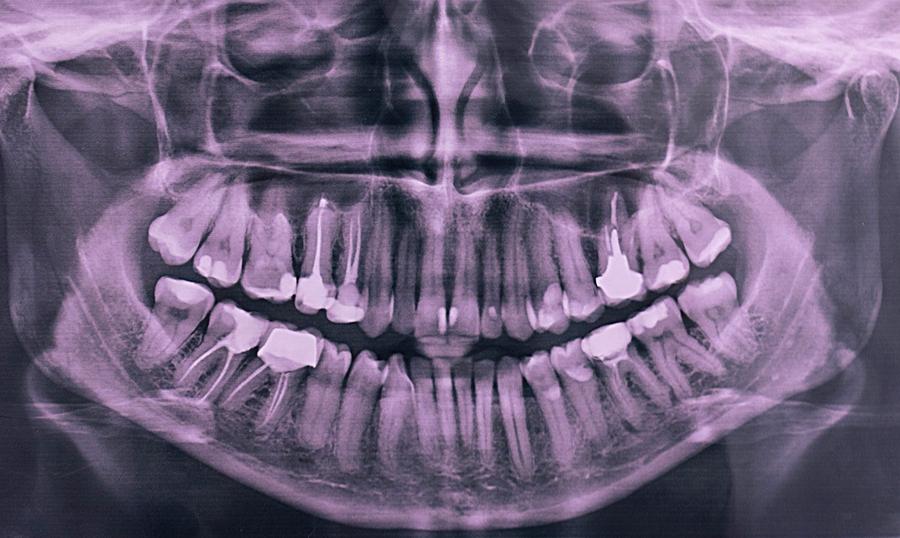

A smile makeover begins with a complete dental assessment using panoramic imaging. Unlike traditional X-rays, Panoramic dental X-rays versus regular dental X-rays in Dubai (البانورامية للأسنان مقابل الأشعة العادية في دبي) provide a full view of your teeth, jawbone, and surrounding structures in one shot. This comprehensive approach allows dentists to identify alignment issues, cavities, or structural concerns that may affect the final outcome. The treatment combines multiple dental procedures, including teeth whitening, veneers, crowns, and bonding, tailored to the patient's unique facial features and oral health condition. Each procedure is strategically planned to achieve a balanced and aesthetically pleasing smile while ensuring functional benefits.